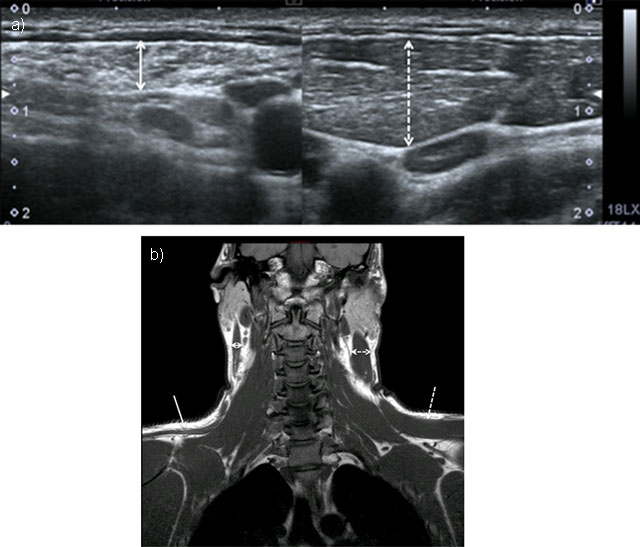

Figure 5

Chronic neuropathy of spinal accessory nerve. Ultrasound showed atrophy of sternocleidomastoid muscle (double solid arrow) compared to normal side (doubled dashed arrow) (5a = FIGURE 13 uploaded online manuscript), confirmed by coronal T1-weighted MRI showing both atrophy of trapezus (solid arrow) and sternocleidomastoid muscles compared to normal side (dashed arrow) (5b = FIGURE 14 uploaded online manuscript).